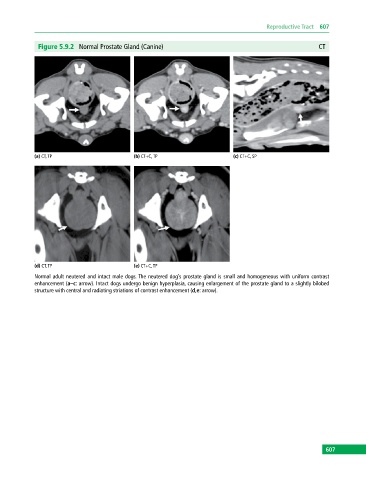

Figure 5.9.2 Normal Prostate Gland (Canine) CT

(a) CT, TP (b) CT+C, TP (c) CT+C, SP

(d) CT, TP (e) CT+C, TP

Normal adult neutered and intact male dogs. The neutered dog’s prostate gland is small and homogeneous with uniform contrast

enhancement (a–c: arrow). Intact dogs undergo benign hyperplasia, causing enlargement of the prostate gland to a slightly bilobed

structure with central and radiating striations of contrast enhancement (d,e: arrow).